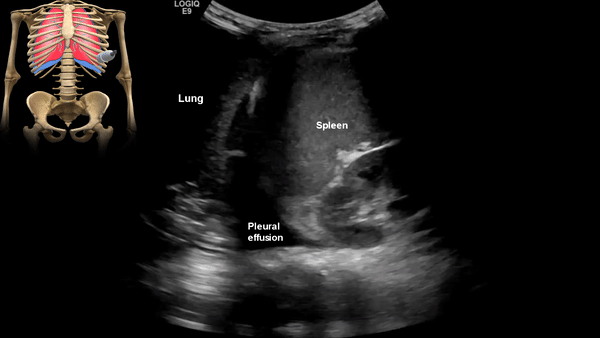

Pleural Effusion

Pleural effusion is a build up of fluid between the layers of the pleura. Scanning subcostally will show fluid above the diaphragm. Scanning intercostally will show fluid anterior the lung. Common causes for pleural effusion is infection, inflammation and malignancy.

The fluid can be anechoic or echogenic in cases of increased exudates, empyema, hemothorax and chylothorax (lymph collection). There may also be septations.

Moderate to large pleural effusion and pleural fluid anterior to lung

Large volume pleural effusion